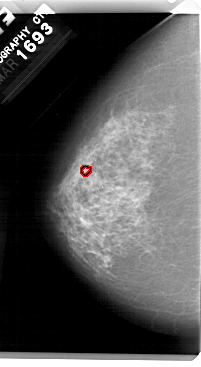

A_1480_1.LEFT_MLO

LEFT_MLO LINES 5491 PIXELS_PER_LINE 3076 BITS_PER_PIXEL 12 RESOLUTION 43.5 OVERLAY

FILE: A_1480_1.LEFT_MLO.OVERLAY

TOTAL_ABNORMALITIES 1

ABNORMALITY 1

LESION_TYPE CALCIFICATION TYPE PLEOMORPHIC DISTRIBUTION CLUSTERED

ASSESSMENT 4

SUBTLETY 1

PATHOLOGY BENIGN

TOTAL_OUTLINES 1

BOUNDARY